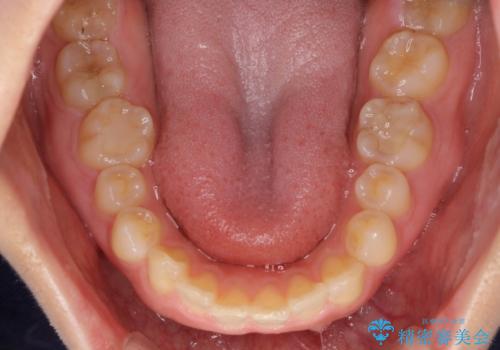

- 前歯の空隙と矮小歯を気にして来院された患者様です。

上下の歯列不正はインビザラインにより整えることとしました。

矯正治療の後に、前歯1歯と奥歯をオールセラミックにて治療することとしました。

矯正治療により矮小歯前後にスペースを作りながら歯列を整え、セラミッククラウン装着後に最終的に歯列と咬合を仕上げました。